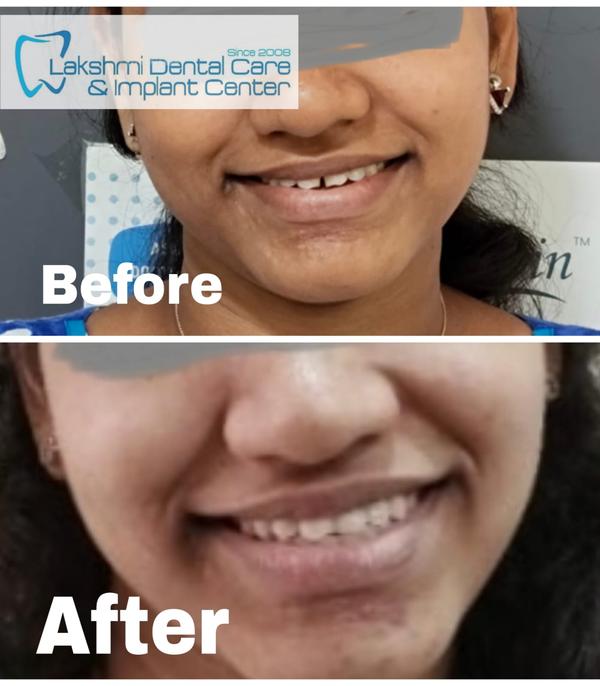

Lakshmi Dental Care And Implant Center (Estd 2008) 35/ 39, Somasundaram Avenue , Sakthi Nagar, Near Porur Post Office , Shell Petrol Station , Porur, Chennai, Tamil Nadu 600102, India +918048036282 drsubramoniam@yahoo.com

Lakshmi Dental Care And Implant Center (Estd 2008) 35/ 39, Somasundaram Avenue , Sakthi Nagar, Near Porur Post Office , Shell Petrol Station , Porur, Chennai, Tamil Nadu 600102, India +918048036282 drsubramoniam@yahoo.com

Lakshmi Dental Care And Implant Center (Estd 2008) 35/ 39, Somasundaram Avenue , Sakthi Nagar, Near Porur Post Office , Shell Petrol Station , Porur, Chennai, Tamil Nadu 600102, India +918048036282